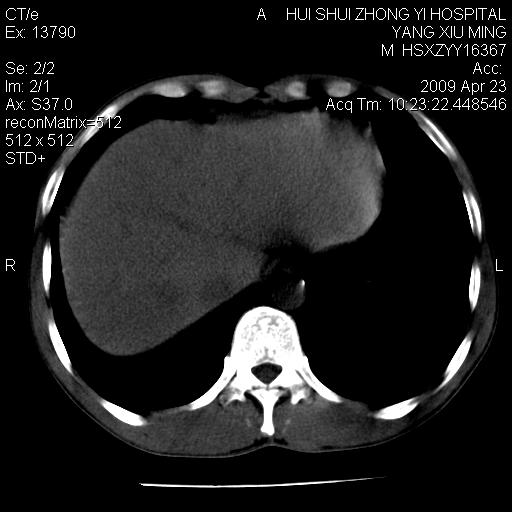

腹膜后淋巴结增大,转移、淋巴瘤?胰腺增大,胰腺炎?占位?颈部考虑增大淋巴结。建议腹部增强扫描。

缺少强化资料,暂考虑胰腺癌广泛转移.

连最基本的ct值都没有测        腹部的窗宽窗位太大了     影响诊断

黑!广泛淋巴结肿大不符合胰腺癌转移。胰腺周围淋巴结肿大致使胰腺看起来大。考虑淋巴瘤可能大。